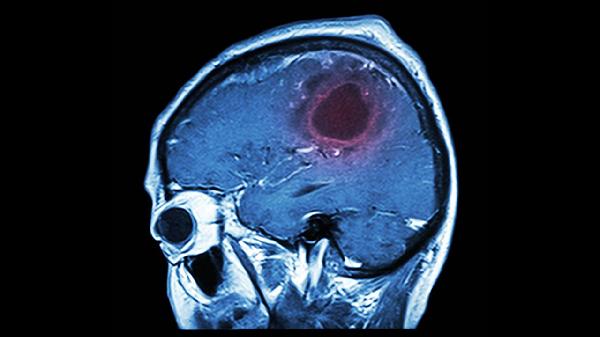

脑溢血早期,常见5个征兆!医生苦劝做好6件事,离脑溢血远点

凌晨急诊室的自动门又一次被撞开,担架床上躺着的中年男性面色潮红,左侧肢体像被抽走力气般瘫软——这是本月第七例错过黄金救治时间的脑溢血患者。当家属哭诉"明明前几天还说头晕"时,医生们总忍不住叹息:那些被当成"小毛病"的身体信号,其实是大脑发出的最后求助。